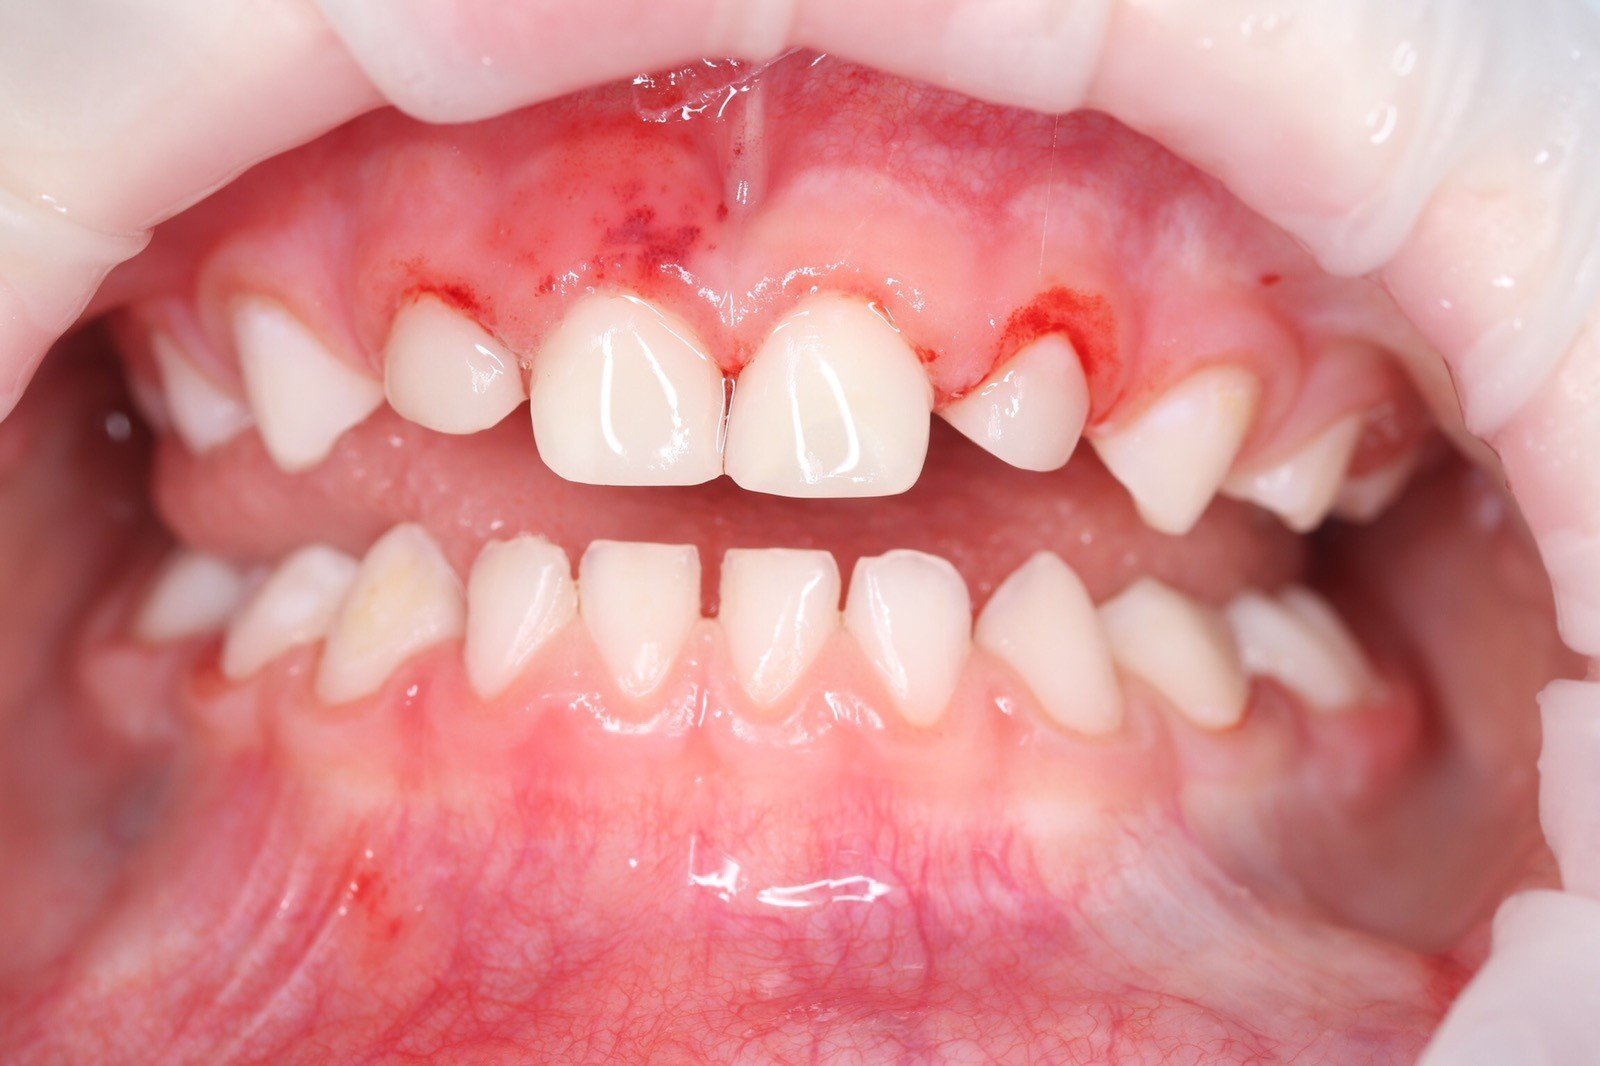

Get the bright white smile you’ve always wanted! Contact us today to get your $139 whitening trays.